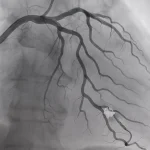

رأب الوعاء: الحل الأمثل لعلاج انسداد الشرايين